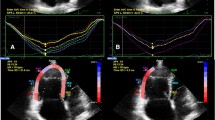

In each patient, 2-dimensional strain analysis was performed offline by use of a dedicated software package (EchoPAC, version BT13) which evaluates real-time tracking of natural acoustic markers during two consecutive 2-dimensional grayscale images taken at a frame rate of 60–80 frames/s. For assessment of RV peak longitudinal systolic strain, images taken at a frame rate of 60–80 frames/s were obtained from the apical 4-chamber view. Three consecutive cardiac cycles were acquired and digitally stored for offline analysis. The RV endocardial border was manually traced in the end-systolic frame. The region of interest (ROI) in each image was automatically generated. The position of the ROI and its width were adjusted manually when the speckle tracking appeared to be poor. The software then automatically tracked and accepted segments of good tracking quality and rejected poorly tracked segments. When all segments of RV were accepted, the regional longitudinal strain curves were obtained for six segments of RV. After that, segmental values of peak longitudinal systolic strain from the basal, mid, and apical segments of the RV free wall were recorded. Representative examples of regional longitudinal strain curves taken from the right ventricle by STE were shown in Figs. 1 and 2.

RV regional longitudinal function

PLSS values from the basal, mid, and apical segments of the right ventricular lateral wall are listed in Table 3. PLSS values from the apical segment of the RV free wall were significantly lower in the PAH group compared with the non-PH group at baseline (− 14.6 ± 5.9 vs. − 22.2 ± 7.5, p = 0.034). At the same visit, PLSS values from the basal and mid segments of the RV free wall were also lower in the PAH group, but these differences between the two groups were not statistically significant. PLSS at the basal, mid, and apical segments of the RV free wall were lower in both groups at follow-up compared to baseline, but the reduction of strain values was statistically significant only in the non-PH group (p < 0.05 for all).

Cut-off values of PLSS of the RV lateral wall for predicting PAH in SSc patients

Among strain values measured in the RV lateral wall, PLSS at the apical segment significantly discriminated SSc patients with PAH from patients without PH (p < 0.05). A PLSS value of − 14.48% in the apical segment of the RV lateral wall (RV Apex) was only 62% sensitive in predicting PAH but was 100% specific in ruling out PAH. PLSS values at the basal and mid segments of the RV lateral wall were not useful for discriminating SSc patients with PAH from patients without PH (Table 5).